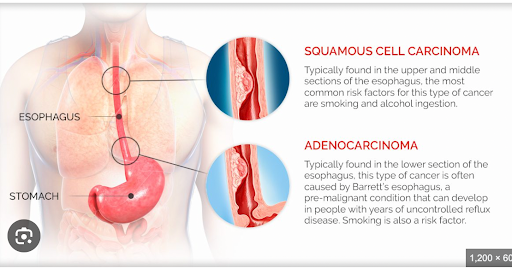

Types of Esophageal Cancer

The two most common types are:

Adenocarcinoma

Esophageal cancer affects the lining of the esophagus and may develop in different sections—upper, middle, or lower—depending on the cancer type.

Types of Esophageal Cancer

The two most common types are:

Adenocarcinoma

- Usually develops in the lower part of the esophagus

- Often associated with long-standing acid reflux (GERD) and Barrett’s esophagus

- More commonly observed in individuals with obesity or chronic digestive conditions

- Develops from flat cells lining the esophagus

- Commonly affects the upper or middle portion

- Frequently associated with tobacco and alcohol use